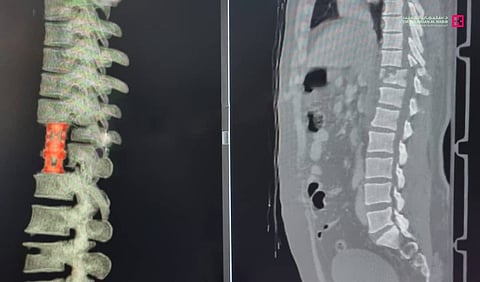

وقال د. ناجي: إن المريض خضع لحزمة من الفحوصات الطبية الدقيقة، فور وصوله إلى المستشفى؛ أبرزها الأشعة المقطعية لكامل الجسم، والرنين المعناطيسي، وكشفت النتائج إصابته بكسر حاد في الفقرة الصدرية رقم "12"، أدى إلى ضغط شديد جداً على النخاع الشوكي، مسبباً الشلل في الأطراف السفلية، ومن ثم أحيل المريض إلى العناية المركزة، وبعد استقرار حالته أخضع لعمليتين جراحيتين، الأولى بالدخول عن طريق فتحة في القفص الصدري من اليسار والعبور إلى منطقة الإصابة في الفقرة الصدرية رقم "12"، وتم فيها إزالة الفقرة المكسورة بالكامل وزرع فقرة صناعية جديدة وتثبيتها ما بين الفقرة "11" والفقرة القطنية "1".

وتابع: بعد انتهاء العملية نُقِل المريض مجدداً إلى العناية المركزة، حيث بقي فيها تحت المراقبة لمدة 72 ساعة، بعدها أجريت له العملية الثانية، وجرى فيها إزالة العظم المكسور وتحرير العصب من الخلف ومن الأمام، عن طريق إزالة الفقرة والعظم، ثم تثبيت الفقرتين "10" و"11" إلى الفقرتين القطنيتين رقم "1" و"2"، وتمت إحالة المريض إلى العناية المركزة، حيث أمضى "4" أيام قيد المراقبة حتى استقرت حالته تماماً، وتخلص من القسطرات، قبل أن ينقل إلى جناح التنويم، وبدأت حالته في التحسن باطراد مع برنامج العلاج الطبيعي المكثف، وبدأ في تحريك أطرافه السفلية شيئاً فشيئاً إلى أن استعاد ولله الحمد قدرته على المشي.